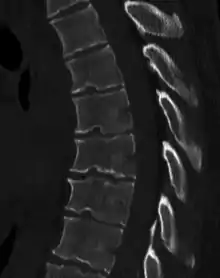

Scheuermann's disease on lateral Xray of the T spine | |